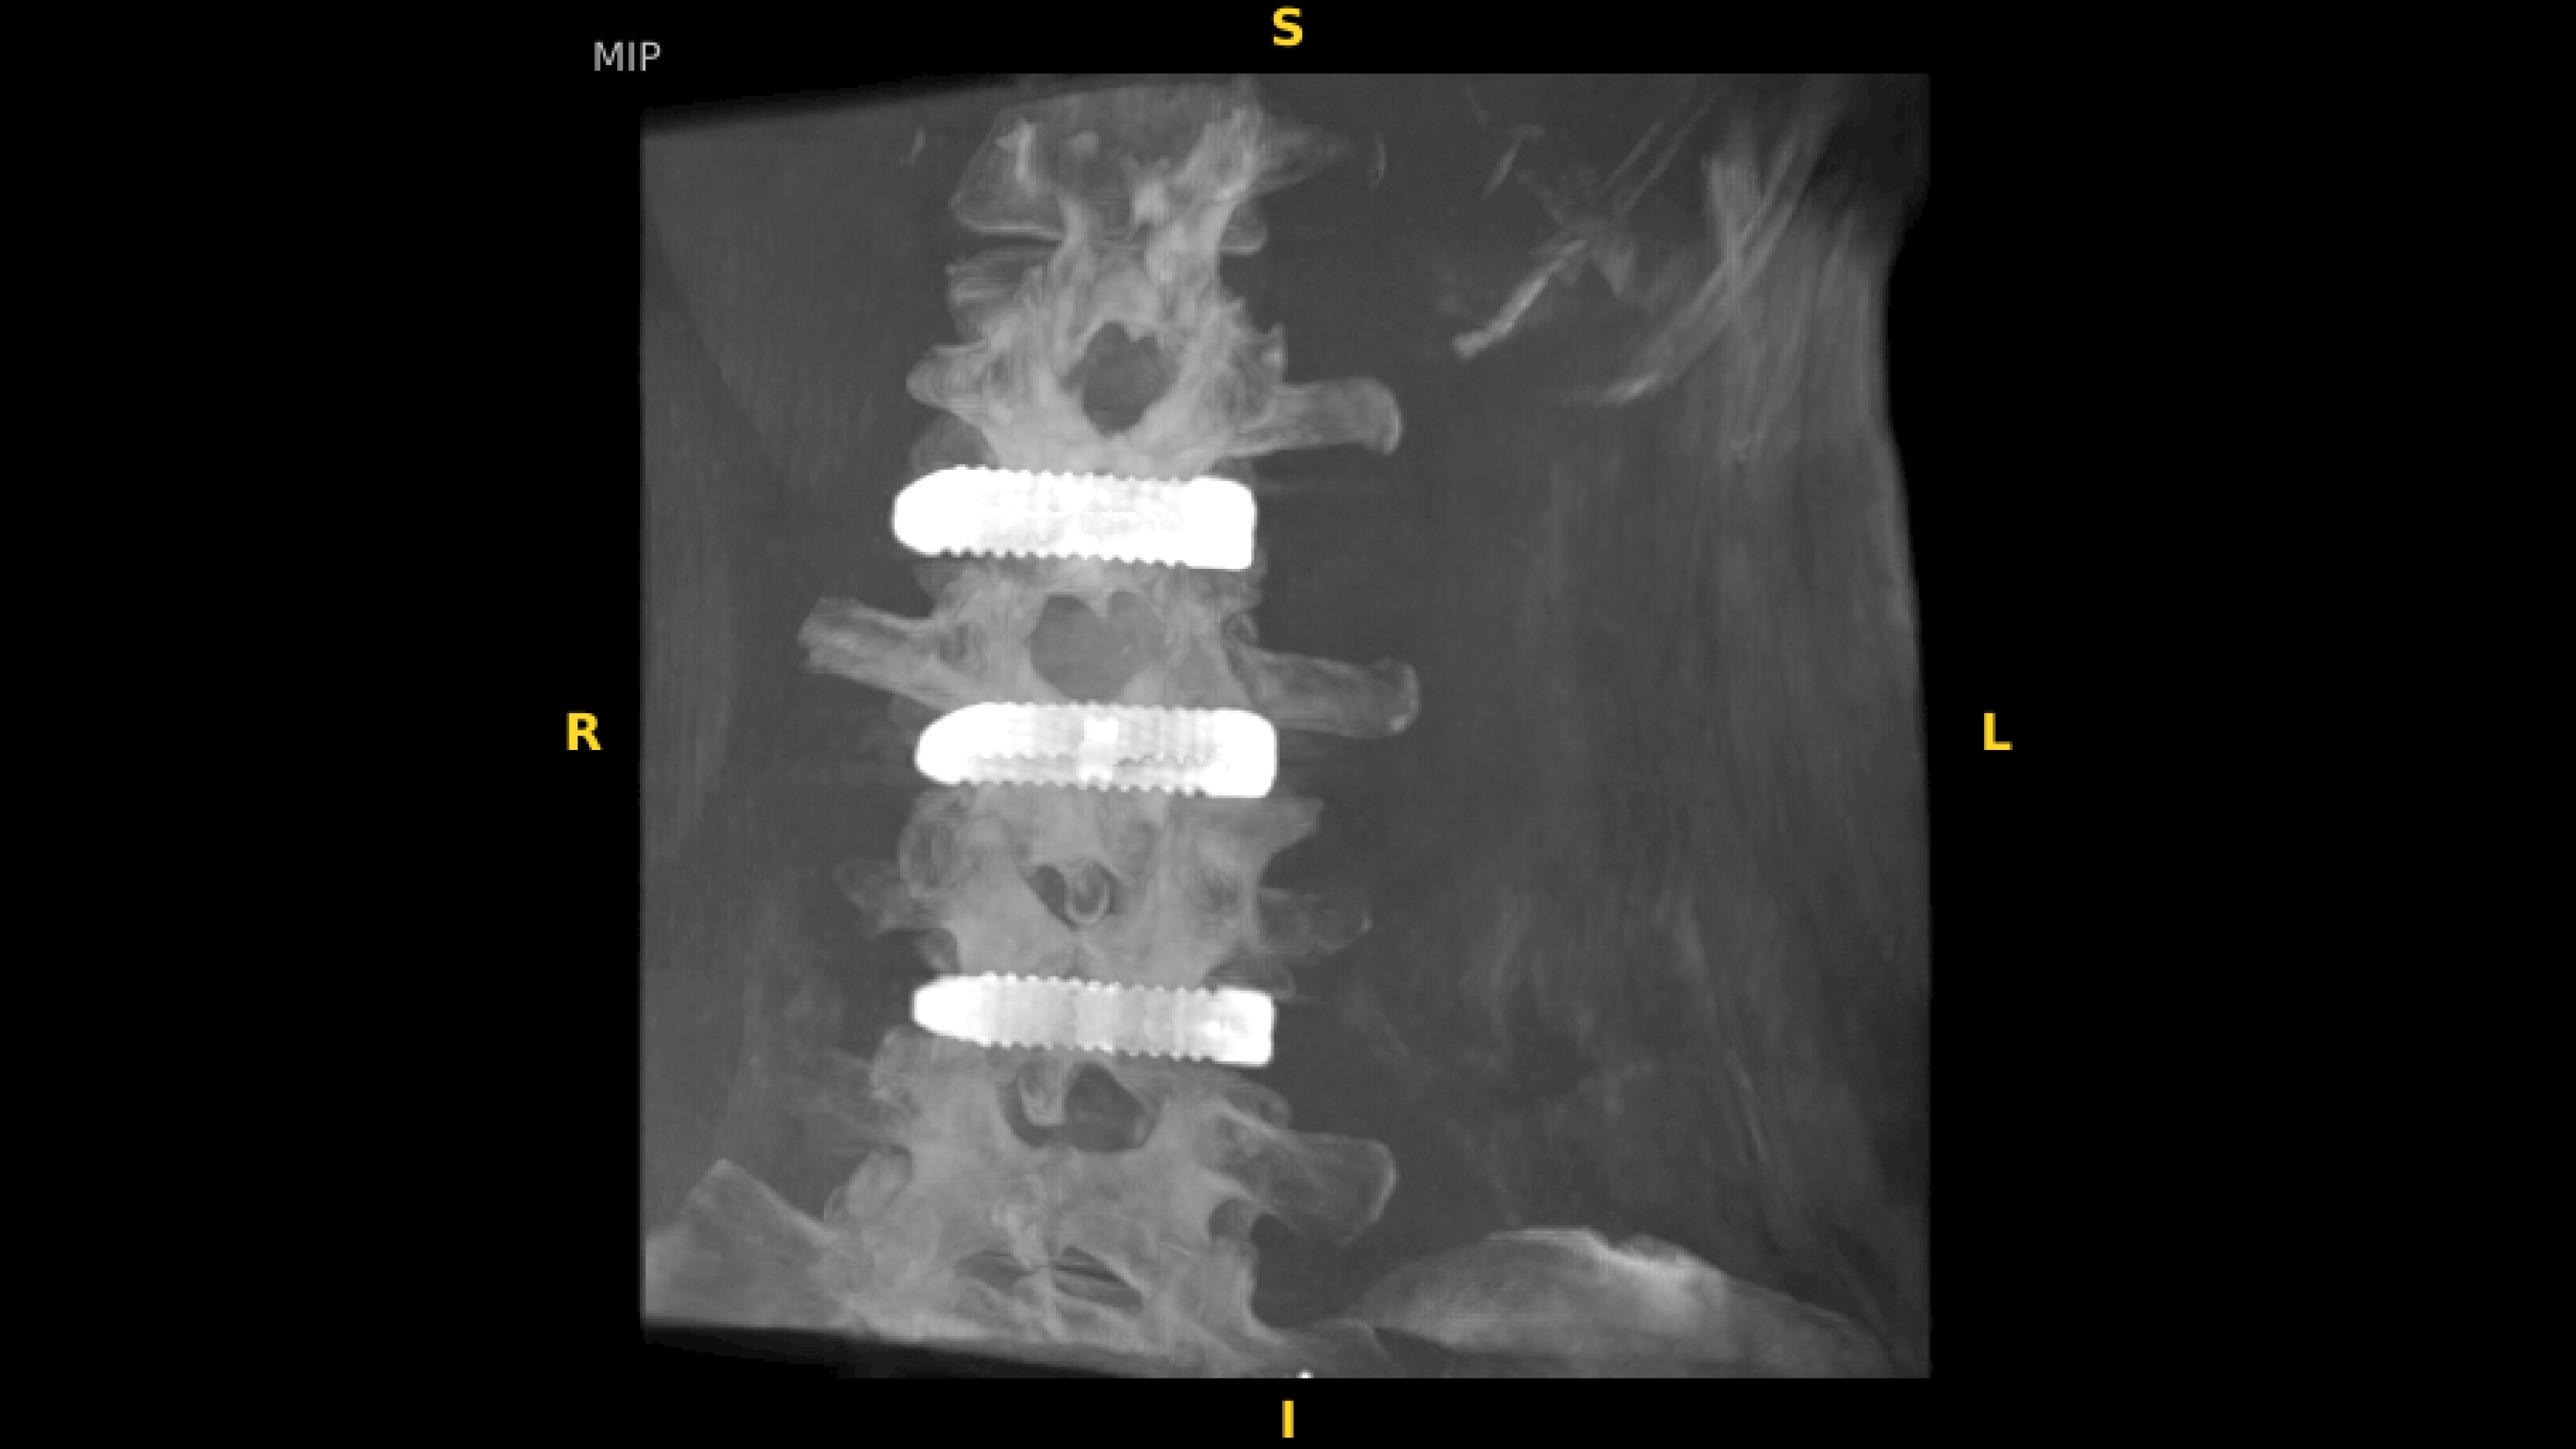

With OEC 3D, comprehensive imaging coverage of 19 cm x 19 cm x 19 cm 3D volumes and exceptional 2D images enables viewing several levels of the spine in the operating room.

The OEC 3D presents five perspectives: Axial, Coronal, Sagittal, MIP, and VR, on a 4K display for clear and detailed review of 3D volumes and 2D images

Review screws with automatic detection and numbering, manually label spine levels, and visualize spinal curvature alignment with Spine Suite, an optional application available with OEC 3D.